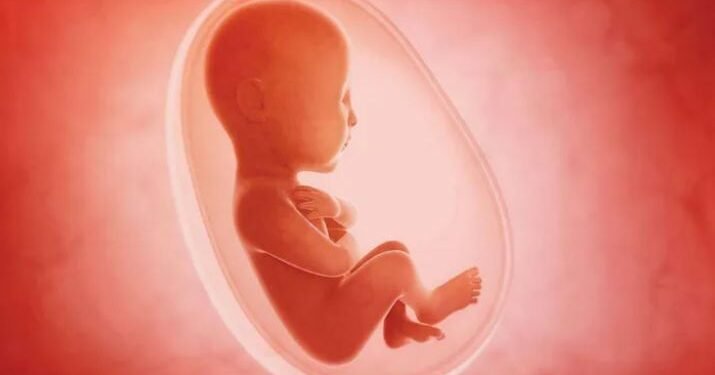

गर्भवतीको मञ्जुरीले १२ हप्तासम्मको गर्भ सुरक्षित गर्भपतन गराउने, विशेष अवस्थामा चिकित्सकको सल्लाहमा २८ हप्तासम्मको गर्भपतन गराउने विषयमा प्रशिक्षण दिइने कार्यक्रम रहेको छ ।

उनले समाजमा गर्भवतीमा छोरी रहेको भ्रूण हत्या रोक्न सामाजिक कार्यकर्ताहरुलाई जनचेतना जागृत गराउने कार्यमा सक्रिय रुपमा लाग्नुपर्नेमा जोड दिए।